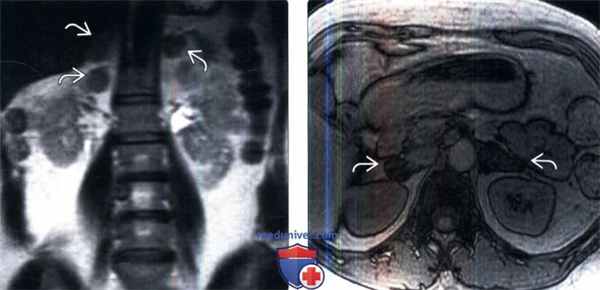

(Слева) У пациента с синдромом Кушинга на коронарном Т2-ВИ в последовательности TSE выявлены утолщенные узловатые надпочечники.

(Справа) МРТ, противофазное Т1-ВИ: у того же пациента установлено подавление сигнала от увеличенных узловатых надпочечников. При поиске причин повышения уровня кортизола (экзогенные глюкокортикоиды, АКТГ -зависимый и АКТГ-независимый синдром Кушинга) план обследования включает сбор анамнеза, лабораторные исследования и визуализацию. В этом случае повышенный уровень кортизола стал следствием аденомы гипофиза.